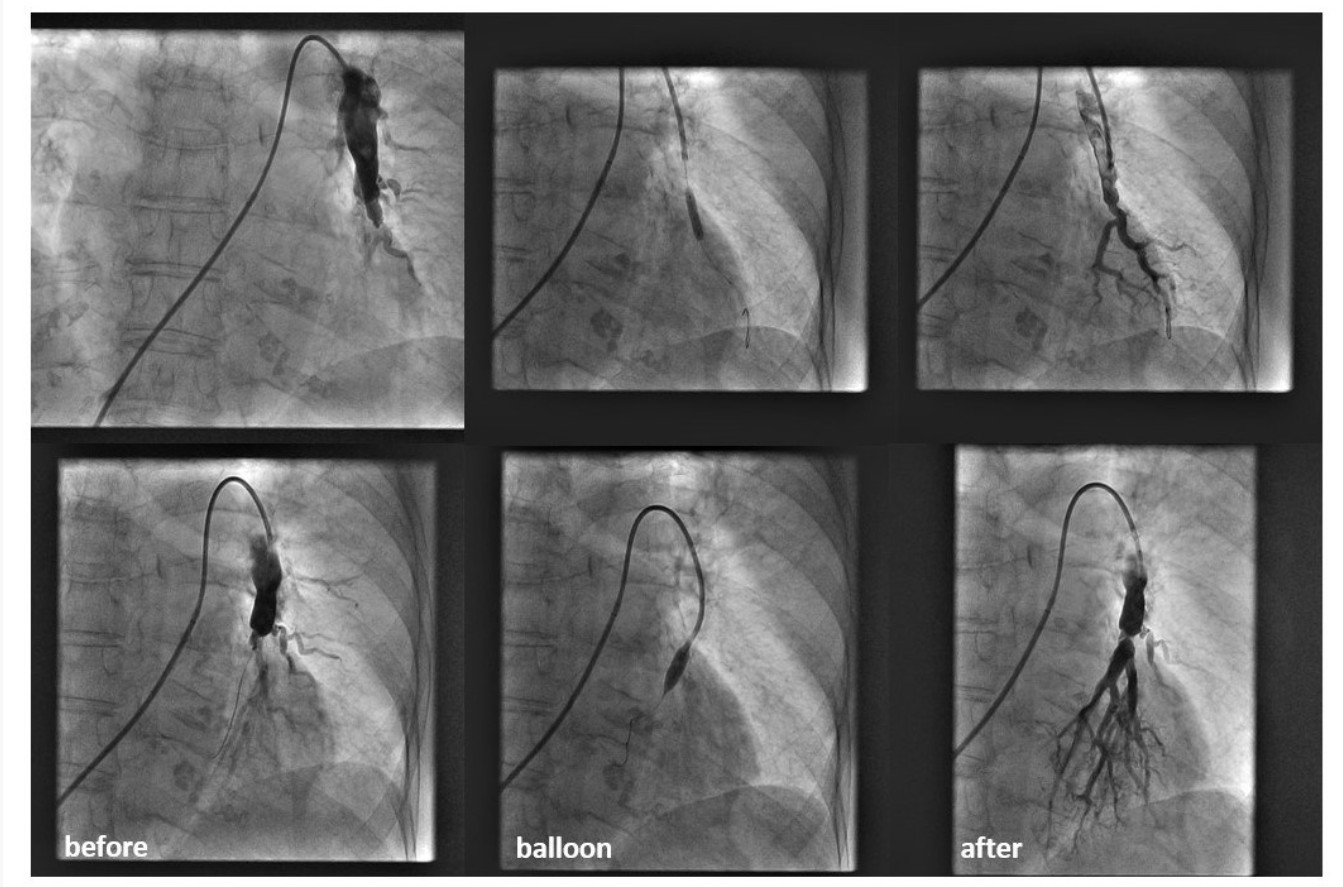

U Kliničkom bolničkom centru Split po prvi je put u Hrvatskoj izvedena balonska angioplastika plućnih arterija kod dvoje bolesnika s kroničnom tromboembolijskom plućnom hipertenzijom (CTEPH), čime je omogućeno provođenje ove napredne minimalno invazivne metode liječenja i u domaćim zdravstvenim ustanovama.

Zahvat su izveli interventni kardiolozi Mislav Lozo i Dino Mirić sa svojim timom, uz tehničku podršku medicinskih sestara i inženjera radiologije, te pod stručnim vodstvom Slobodana Obradovića s Vojnomedicinske akademije u Beogradu, koji iza sebe ima više od 200 ovakvih zahvata. Oba pacijenta brzo su se oporavila i izrazila veliko olakšanje nakon zahvata.

„Najmanje 40 posto pacijenata s CTEPH-om nisu kandidati za operaciju zbog tehničkih ili zdravstvenih razloga, zbog čega je balonska angioplastika izuzetno važna alternativa. Uvođenjem ove metode pokazujemo kako splitska kardiologija prati svjetske trendove i podiže kvalitetu skrbi za bolesnike s plućnom hipertenzijom“, poručio je Lozo, zahvalivši kolegama i vodstvu klinike na podršci.